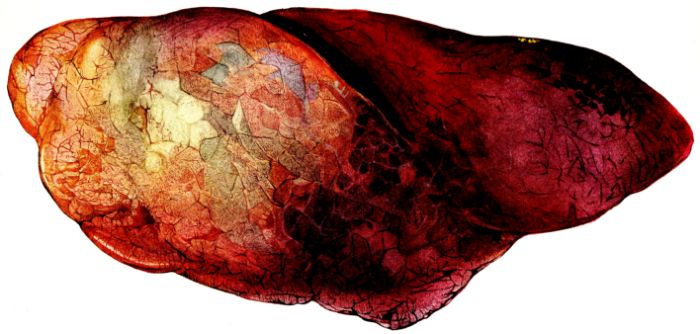

19The lungs are extremely voluminous (12, 17) due in part to an accumulation of liquid within them. This finds its way into the trachea and completely fills the latter structure with blood-stained, syrupy fluid, with purulent material, or with a mixture of these (2, 90, 107, 157, 162). At first the pleural surface is smooth and often quite even, but on closer inspection, a minute granulation is suggested. In many cases even close examination does not allow the conclusion that an exudation of anything but serum has occurred through this membrane, except in localized foci. These foci more frequently involve the interlobar pleura and that of the lower lobes (112, 143). The volume of the lungs, often great enough to obliterate the pericardial area, is one of the two most characteristic features of the external examination. The other feature is their color. Small, bright red hemorrhages may occur anywhere. The larger patches are the most striking. Violet, purple, or dark brown areas, irregular in shape and distribution, are more frequently found on that portion of the pleura over the lower two-thirds of the lung. Between the deeply colored zones, there are pale pink areas which involve the lowermost edge to the least degree, the anterior margin somewhat more, and the apex of the lung most of all. The darker portions just referred to may project above the surface and may be circumscribed, resembling huge, fresh hemorrhagic infarcts (41, 108). The alveolar walls are not seen through the pleural surfaces in these darker zones. The pale pink areas, usually at the level of the more intensely colored zones, may be elevated and the dilated air sacs are distinctly made out through the pleura (Fig. XIII). At the hilum, the lymph glands are large and soft. When cut, fluid escapes and is often blood-stained. The cross section may present a distinct, diffuse, hemorrhagic appearance (162). At the hilus, too, the lymphatics, distended here and there over the surface of the pleura, are most affected. The congested bronchial mucous membrane and the exudate in these structures has been described.

After removal, the lung retains its shape, but is more flaccid than the consolidated lung of lobar pneumonia. It cuts with very little resistance and immediately a large amount of a syrupy, pink fluid escapes and obscures the entire area. With the fluid scraped away, the variations in the consistency of the lung become visible. The pale areas around the borders and chiefly at the apex in which the air sacs are discernible with the naked eye, sink slightly below the remainder of the surface, and the pleural edge inverts. The individual lobules of the lung in these areas are more conspicuous than normal, because the interstitial tissue bearing the lymphatics and vessels, as well as that around the bronchi and larger blood vessels, does not lose its edematous appearance as quickly as the alveoli (40, 92, 110, 164), and, consequently, these grey lines and points stand up somewhat more prominently.[6] In contrast with the paler areas which are prone to slight collapse, the remainder of the cross section retains its more smooth and even surface. The alveolar walls are not distinctly made out, but the terminal bronchioles often make themselves evident by the nature of the material which is within and by their distinct dilatation (1, 67, 110, 149, 162). The more firm areas stand out, too, on account of their difference in color. The scheme is not unlike that seen on the pleural surface, and while dark, almost black, infarct-like areas occur on the cut surface, the solid areas are more likely to be translucent, dull, light red, brown or even grey. They have a surface similar to a very fresh, tuberculous, gelatinous pneumonia, but the color differs from the cloudy grey of the latter on account of the admixture of blood in the exudate and the great congestion of the vessels (Fig. XIV).

The well developed post-mortem muscular rigidity, the lividity of the dependent parts, of the face with its mucous membranes, and often of the trunk, the jaundice variable in extent, the crusts of blood on the nares and mouth, and the splanchnic dilatation are features which prepare for the gross picture presented by the thoracic organs. The increased moisture within the pleural cavities associated with the even, translucent pleural surface, whose dilated lymphatics become more and more prominent towards the hilum, the large succulent lymph glands, and the exudate in the bronchial tree, are all striking, but more characteristic of the gross picture, is the great increase in volume of the lung itself, mottled 20with brilliant colors. The lung, too, is very wet and on section, after the syrupy, blood-stained fluid escapes from the less definitely consolidated zones, the latter appear, not as the usual granular, firm areas of hepatization, but have more the consistency of a gel, and also its translucence. Characteristic of this disease as these changes may be, the specificity of the fundamental lesion in the respiratory tract, becomes more emphatic after study of its histology (92, 162).